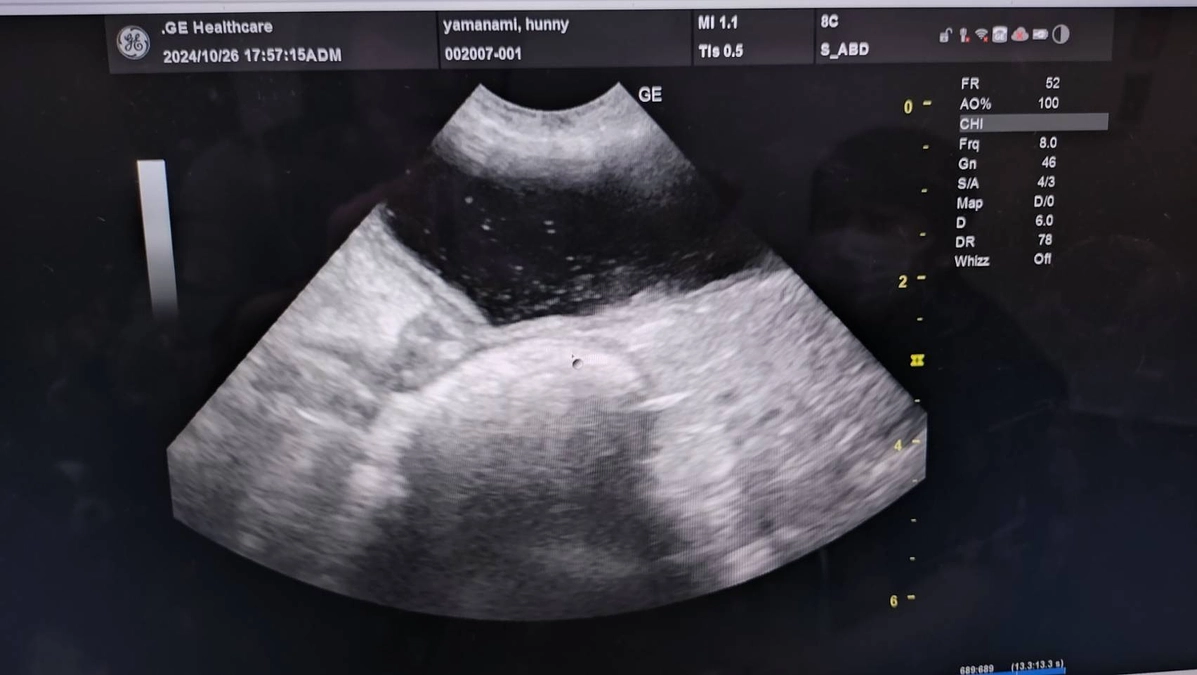

血尿は細菌性膀胱炎と診断された。

エコー写真→キラキラ白く写っているのが菌、脂肪や結石様のもの浮遊物

腎臓結石あり→悪さはしていない

右、左の腎臓も変形などなし

今のところ腫瘍とかは確認できるものはなさそう

とのこで、抗生剤の内服していくことになった。